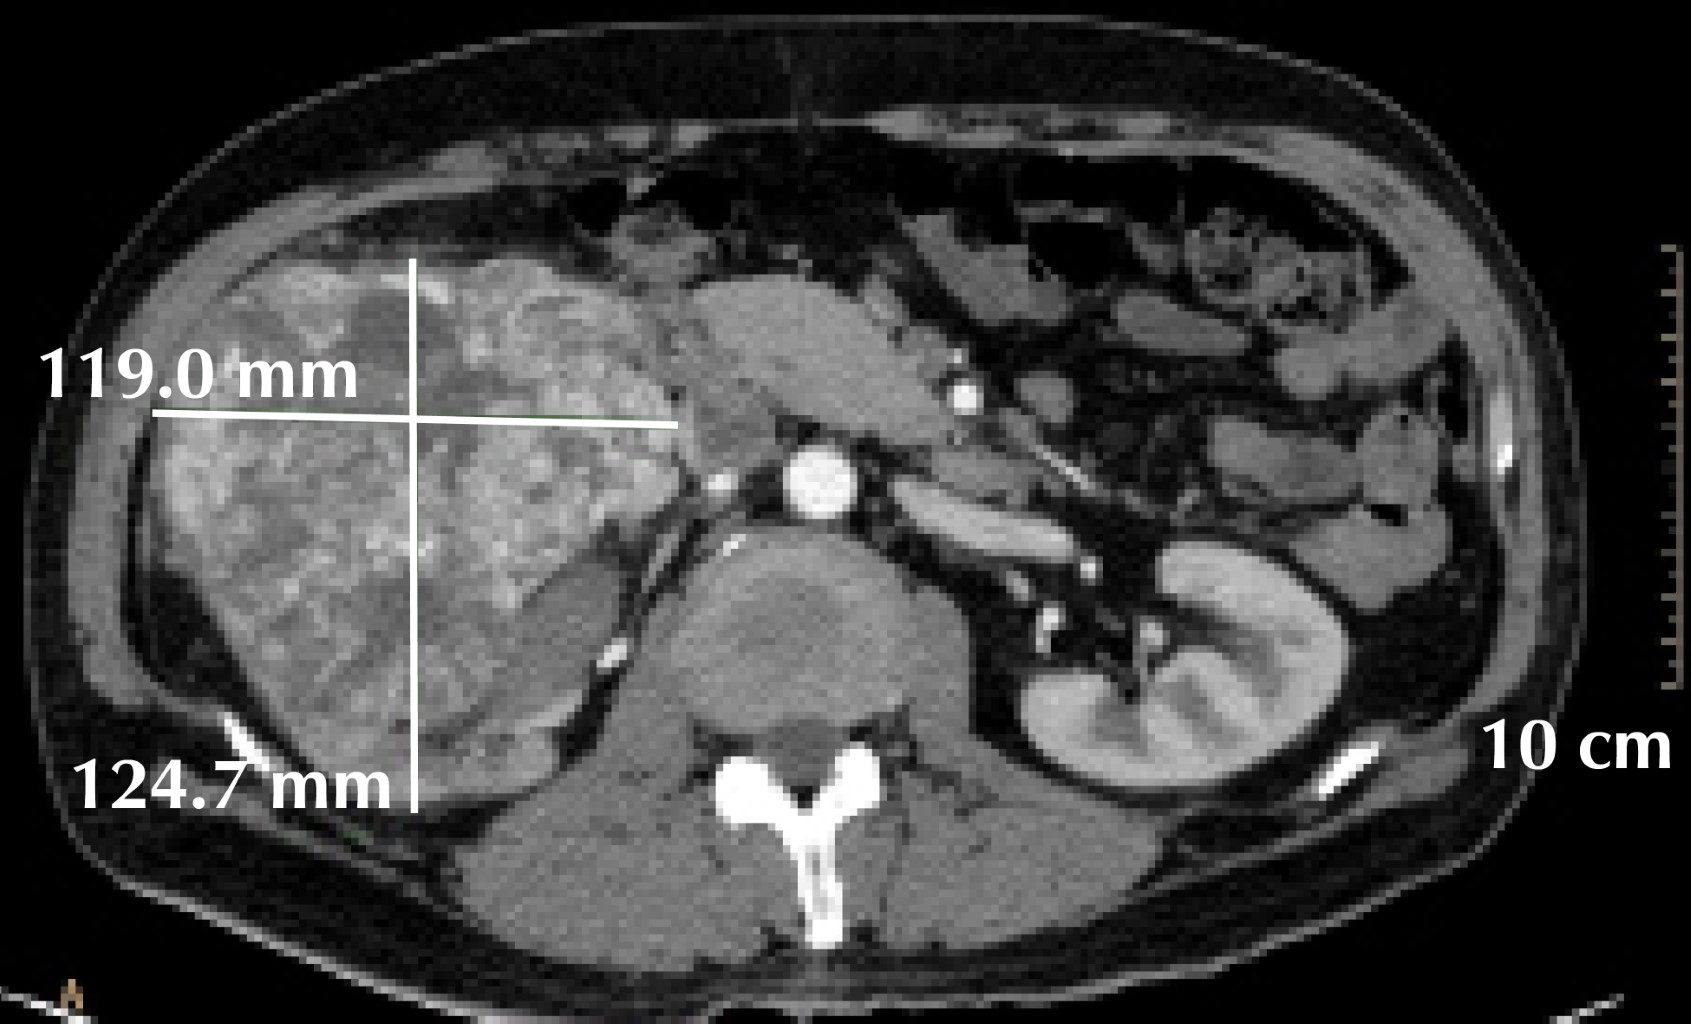

Figure 4